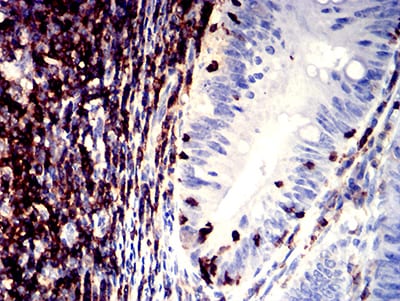

Immunohistochemical analysis of paraffin-embedded human tonsil tissues using CD11a mouse mAb with DAB staining.

Immunohistochemical analysis of paraffin-embedded human rectum cancer tissues using CD11a mouse mAb with DAB staining.